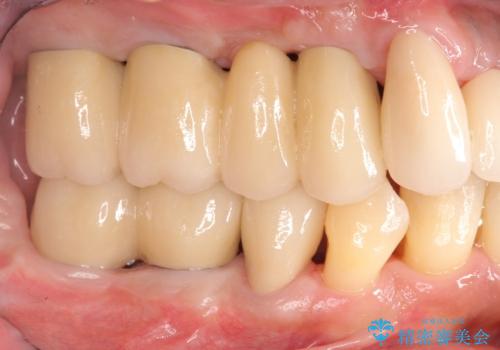

インプラント・ブリッジ補綴を含む、歯周病全顎治療

長期間にわたる治療後、歯に対する意識も大きく変わりプラークコントロールも非常に良くなりました。

数ヶ月に一度のチェックをしっかりと行い、ブリッジ・インプラントが長期間使用できるようメンテンスを行っていきます。